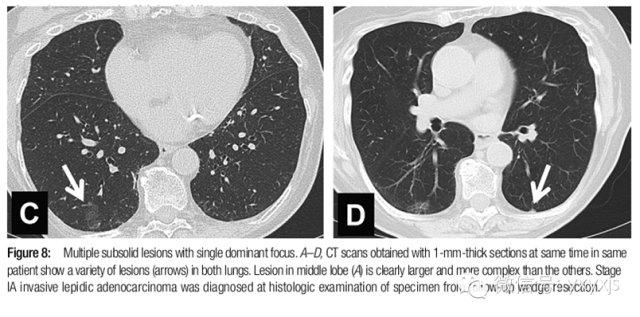

6有突出病灶的多发GGO,主要病变需进一步处理。首次3月后复查,病灶若持续存在,建议对较大病灶给予更积极的处理,尤其是病灶内的实性成分大于5mm者。

术式推荐胸腔镜楔形手术或肺段切除。

术后病人每年随诊,至少持续3年。